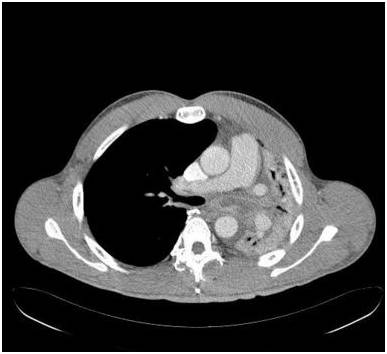

胸部前后位示弥漫不均匀的异常密度影,左肺体积缩小,左肺门区肿块样影与心膈角呈钝角。未增强纵隔窗CT示左肺肺不张,左主支气管完全受阻。增强CT示左主支气管及其段支气管内非强化的肿块。最小密度投影示左肺叶远端支气管重度狭窄,左主支气管及以下层面受阻。